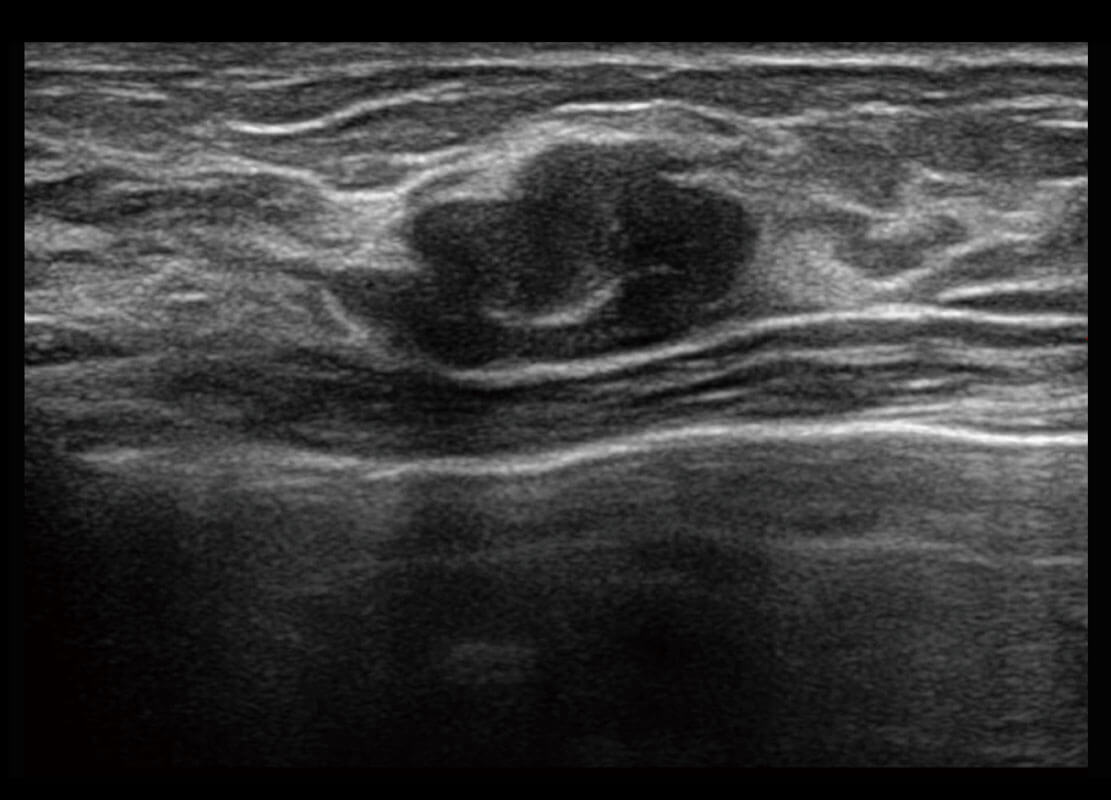

乳腺超声 / 新生儿

P60搭载宽频带线阵探头、宽景成像、弹性成像技术,为您提供乳腺应用方案。P60支持高频相控阵探头、线阵探头、腹部高频探头、腹部微凸探头等,丰富的探头群搭载敏感的彩色血流成像,适用于新生儿多种脏器检测要求,满足新生儿筛查需求。

• 乳腺导管癌

• 乳腺癌显微血流

• 新生儿肝血管癌

• 新生儿脊髓圆锥

• 新生儿心脏